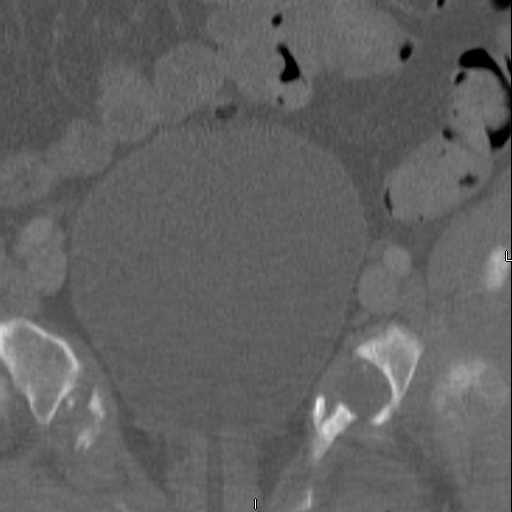

Here are a recent patient’s example slides...

3 Months After Fall

Continued Pain & Immobility

(+) Instability to Compressive Manual Exam

Pelvic CT Scan - 3 Months After Fall

Sacral Injuries

Ramus Fractures

Percutaneous Fixation

(B) Ramus-Retrograde

2 TransIliac-TransSacral

Upper Segment